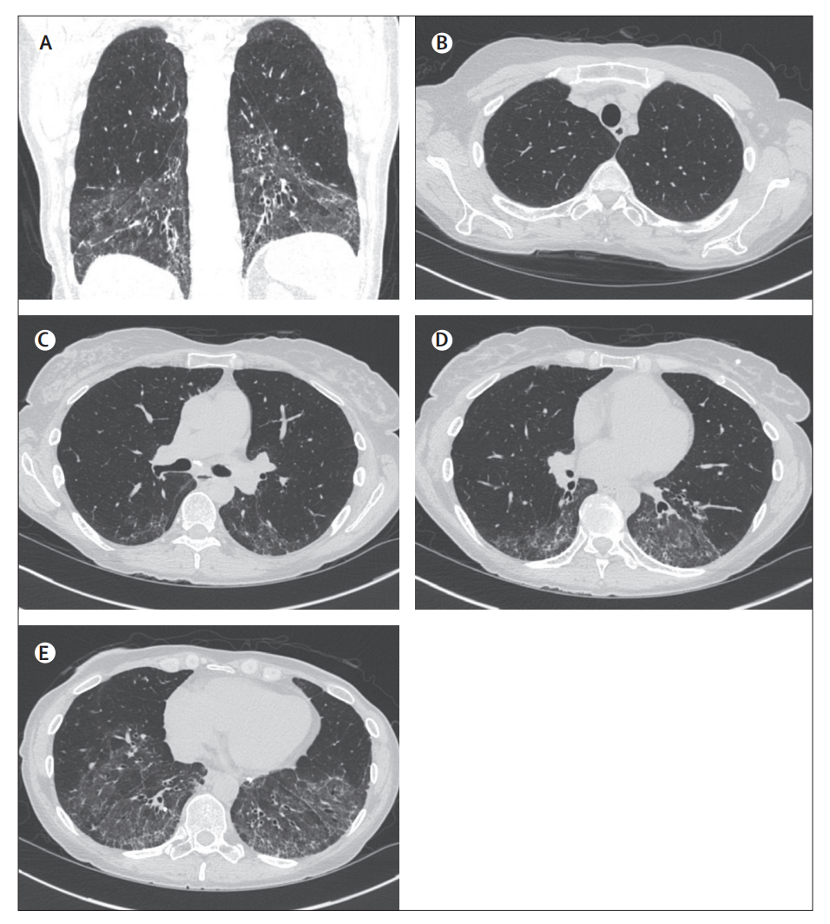

2) HRCT扫描 — 肺部薄层(3mm或以下)HRCT扫描有助于ILD的评估。SSc相关性ILD的HRCT模式反映了特发性间质性肺炎的常见组织病理学模式,如纤维性NSIP、UIP和小叶中心性纤维化。NSIP最常见的HRCT表现为肺网状纹理增多、牵拉性支气管扩张、肺叶体积减少和磨玻璃样不透光区,主要受累区域为下肺部,见图1。

图1. HRCT冠状位(A),矢状位(B-E)显示纤维化、非特异性间质性肺炎,伴有玻璃影、网状纹理、牵拉性支气管扩张